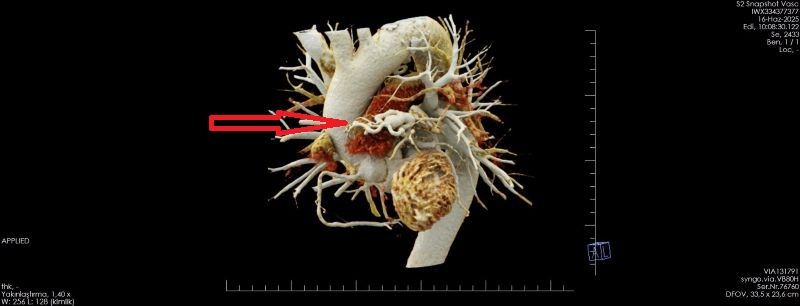

OLGU:

Koroner arterin pulmoner artere füstülizasyonu ile Koroner BT Anjiyografi ile demosterize edilmiş olgu örneğidir.